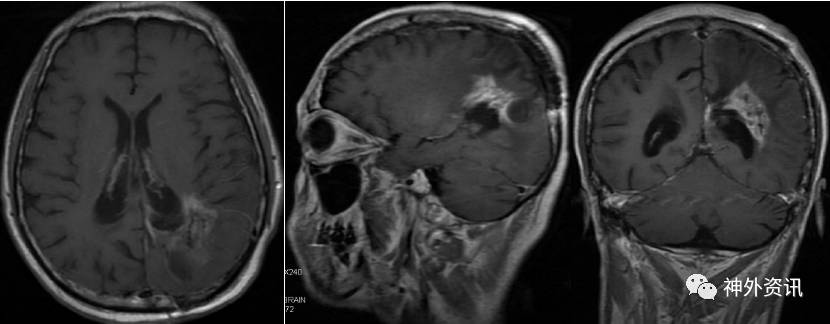

手术顺利,术后予以脱水、激素(甲强龙40mg Qd)及对症支持治疗,患者病情平稳。复查头颅MRI增强(2016.8.22):左侧脑室后角旁不规则形异常信号,呈T1、T2等信号,内见小片T2稍高信号,增强后呈明显强化,强化欠均匀,周边见大片T1低信号、T2高信号水肿区。对比前片(2016-07-12)肿块明显缩小(图6)。

图6. MRI检查:左侧脑室后角旁不规则形异常信号,呈T1、T2等信号,内见小片T2稍高信号,增强后呈明显强化。

出院后1月复查头颅MRI增强示(2016.9.21):左侧脑室后角旁不规则形异常信号,呈T1、T2等信号,内见小片T2稍高信号,增强后呈部分强化。对比前片(2016-08-22)左侧脑室后角及三角部旁病灶明显缩小(图7)。

图7. MRI检查:左侧脑室后角旁不规则形异常信号,呈T1、T2等信号,内见小片T2稍高信号,增强后呈部分强化。

目前患者病情稳定,已经密切随访半年余,除右侧同向性偏盲外,无其他明显症状和体征,KPS评分90分。复查头颅MRI增强示(2017.02.13):左侧脑室后角旁不规则形异常信号,呈T1、T2等信号,内见条状T2低信号影,增强后呈部分强化,周围脑组织水肿,左侧脑室后角扩张。对比前片(2016-08-22)左侧脑室后角及三角部旁病灶相仿(图8)。

图8. MRI检查::左侧脑室后角旁不规则形异常信号,呈T1、T2等信号,内见条状T2低信号影,增强后呈部分强化